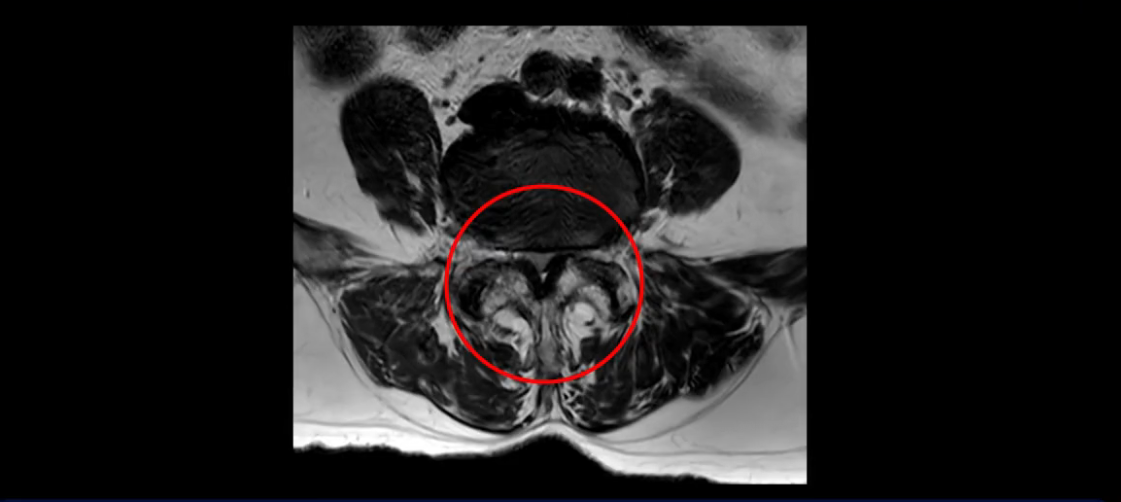

또 척추관협착도 매우 심합니다.

척추관이 심하게 좁아져 있습니다.

이렇게 여러 마디가 안 좋고 뼈도 밀려 나가 있으니까 나사박는 수술해야 하는데, 대학병원에서도 수술을 한 번에 못 하고 두 번에 나눠서 해야 한다고 들으셨습니다. 왼쪽으로 신경가지가 빠져나가는 추간공도 많이 좁아져 있습니다.

이렇게 신경 구멍들이 좁아져 있고 신경이 눌리니까 엉덩이와 다리가 너무 저리고 아파서 아예 일어서질 못하니까 휠체어를 타고 병원에 내원하셨는데요. 그럼 어떻게 이분처럼 신경이 눌려있는 환자분들을 수술 없이 치료해서 잘 걷게 만들고 엉덩이와 다리가 저리고 아픈 증상이 사라지게 할까요? 지금부터 설명해 드립니다.